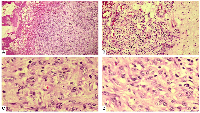

A wide local excision was performed under local anesthesia. Gross examination showed a well-encapsulated mass. The specimen was submitted for HPE, which gave the diagnosis of EHE with tumor-free surgical margins (Figure 2). The tumor cells exhibited minimal nuclear atypia, vesicular nuclei, and eosinophilic cytoplasm. The mitotic rate was low (<1 mitosis per 10 high-power fields), with no evidence of necrosis. Occasional intracytoplasmic lumina containing erythrocytes were noted. The diagnosis was further confirmed by immunohistochemical staining, which demonstrated strong positivity for endothelial markers CD31, CD34, and factor VIII-related antigen. Fusion gene studies couldn’t be performed due to financial constraints.

Histologically, epithelioid hemangioendothelioma (EHE) typically shows cords, strands, and nests of epithelioid endothelial cells embedded in a distinctive myxohyaline stroma [8]. The tumor cells are polygonal to slightly spindled, with eosinophilic cytoplasm, vesicular nuclei, and small nucleoli. Intracytoplasmic vacuoles containing erythrocytes, often a subtle indicator of vascular differentiation are present in many cases [9]. Mitotic activity is usually low (<1–2/10 high-power fields), nuclear atypia is generally mild to moderate, and tumor necrosis is uncommon but, when present, may indicate more aggressive behavior. Occasional multinucleated giant cells and stromal sclerosis may also be seen [10].

Immunohistochemically, EHE demonstrates diffuse positivity for vascular markers such as CD31, CD34, ERG, and factor VIII-related antigen, with CD31 being the most sensitive and specific endothelial marker. The tumor is typically negative for epithelial markers (cytokeratin AE1/AE3, EMA) and S100, aiding in the exclusion of carcinoma, melanoma, and most epithelioid sarcomas [11]. CAMTA1 immunoreactivity can also serve as a surrogate for the presence of the WWTR1–CAMTA1 fusion gene [12].